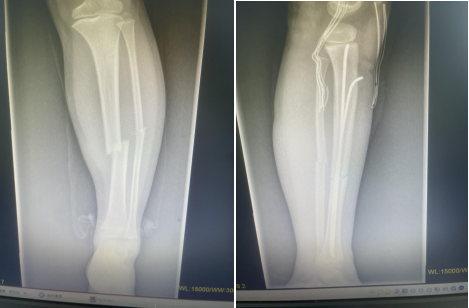

弹性髓内钉技术的特点:

①闭合整复骨折;

②保护了骨折周围的软组织附着和血运,骨折愈合快;

③利用其弹性和双“C”形的固定模式形成髓内支架,骨干周围的肌肉构成软组织框架,达到相对稳定的生物学固定;

④不损伤长骨干两端的骺板;

⑤住院时间短,利于早期返校复学。

因此,该技术是一种微创、安全、有效、并发症少的内固定方法,适用于儿童长骨干横形、斜形及短螺旋形骨折,对肱骨和股骨近、远端干骺端骨折及桡骨颈骨折如应用得当也可获得满意的治疗效果。目前,弹性髓内钉技术在国内外已成为儿童四肢长骨干闭合性骨折治疗的首选方法。

术后应使用石膏或支具固定 6~8,尤其是不稳定性骨折。石膏或支具固定有助于缓解疼痛和减少膝关节周围软组织激惹。当X线片上有连续骨痂出现,可开始部分负重行走。弹性钉取出时间可根据骨折愈合时间及功能恢复情况而定,学龄期儿童寒暑假期间取出内固定为宜。弹性钉留置时间过长,可能会增加取出的难度。股骨干骨折4~5个月可获得坚强愈合;肱骨和胫骨通常需要 3~4 个月;尺桡骨双骨折约 6 个月可获得坚强愈合。而干骺端骨折通常 6~8 周愈合,术后 3 个月即可取出内固定。(骨二科)